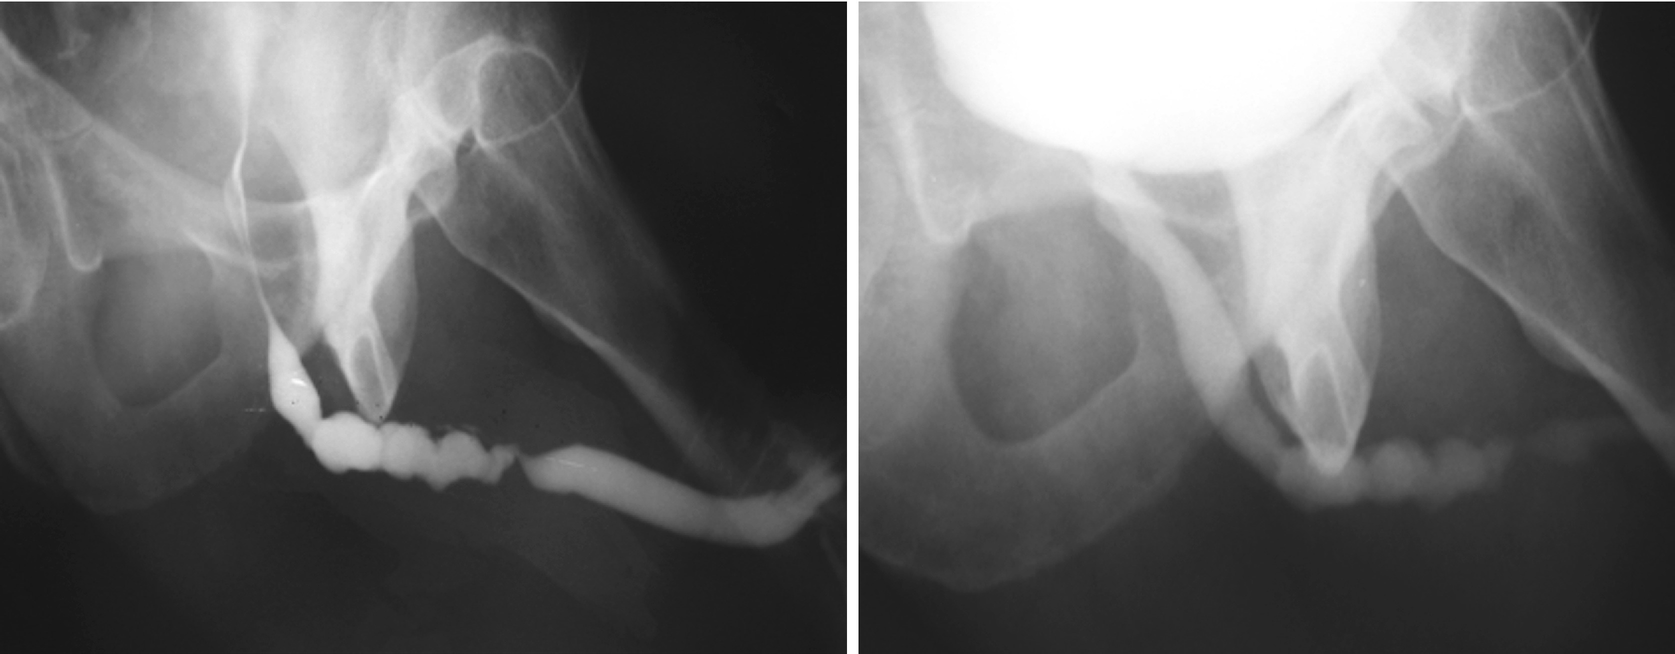

5.3.2 Retrograde Urethrogram and Voiding Cystourethrogram

A properly performed and normal retrograde urethrogram . The four distinct parts and bladder are labelled accordingly: p = penile urethra, b = bulbar urethra, m = membranous urethra, pr = prostatic urethra, b = bladder

These two urethrograms on the same patient without and with proper oblique positioning demonstrate the importance of proper positioning during urethrogram. Without a sufficient oblique positioning the presence and length of stricture can be underestimated